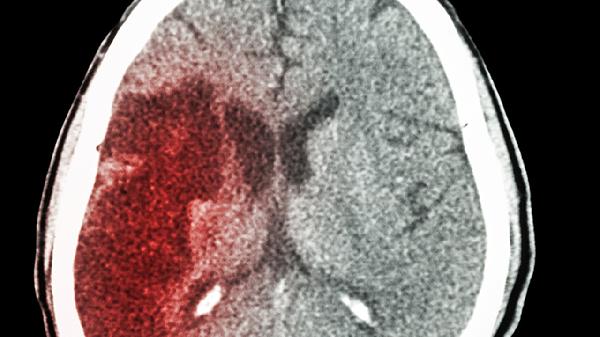

交通事故导致的脑出血后遗症主要有运动功能障碍、认知障碍、语言障碍、情绪行为异常、癫痫发作等。脑出血后遗症的严重程度与出血部位、出血量、救治时机等因素密切相关,需通过康复治疗和长期护理改善生活质量。

脑组织瘢痕形成可能成为异常放电病灶,约20%患者在出血后1年内出现癫痫。发作类型包括局灶性发作和全面性强直阵挛发作。预防性使用左乙拉西坦片、丙戊酸钠缓释片等抗癫痫药物需根据脑电图结果个体化决策。